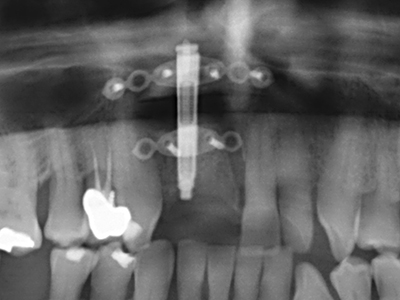

Пиезохирургията има допълнителни предимства при събиране на костни блокове. В допълнение към високата прецизност при остеотомията, описана по-горе, употребата на фините режещи накрайници значително намаляват загубата на материал. Голяма загуба на материал по време на събиране може да се очаква с дебелите накрайници, особено при употреба на борери Линдеман (Lakshmiganthan, Gokulanathan et al. 2012). Базалното разделяне, което е необходимо, особено за присадка на блок при ретромолар, е улеснено от специално създадени правоъгълни триони. В резултат на това, пиезохирургията е разглеждана като прецизна, улеснена и безопасна процедура за събиране на костни блокове в ретромоларното пространство (Happe 2007) (Фиг. 1-12).

Когато се извършват хирургични процедури върху кост в непосредствена близост до чувствителни структури като кръвоносни съдове или нерви, ротиращите инструменти създават значителен риск за ятрогенно нараняване. Пиезоелектрическите апарати могат да бъдат от помощ при препарация на костно покритие и отстраняване на твърда кост близо до нерви, особено за оголване на нервите след ятрогенно нараняване, както и по време на латерализация на нервите за резекционни и реконструктивни процедури или поставяне на имплант (Фиг. 17-20). Лекият контакт между пиезонакрайника и нерва по принцип не води до нараняване, но ако действате непредпазливо с трионообразни движения или приставки за остатъчен костен субстрат, може да причините временно или перманентно увреждане на нерва. Въпреки това, рискът от увреждане се счита за много по-малък, отколкото при употреба на триони или ротиращи инструменти (Pereira, Gealh et al. 2014).